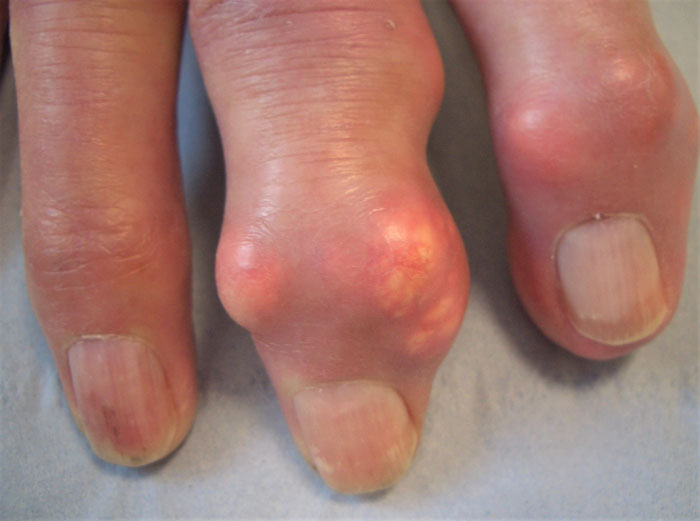

Apart from very painful disease flares, gout can also cause damage to joints with resulting chronic usage-related pain; increased likelihood of the patient needing knee or hip joint replacement, even if the individual has not experienced flares in those joints;4 tophi, disfiguring subcutaneous nodules (see figure 1); and reduced quality of life.5

Patients may also present with subcutaneous tophi, especially older people. Tophi particularly occur on extensor surfaces of toes, fingers, heels, knees and elbows, appearing as nodules with heterogeneous consistency (unlike homogeneous rheumatoid nodules), sometimes with white-yellow discoloration – urate crystals are white. Patients may report previous gout flares but some present just with tophi or chronic joint symptoms.